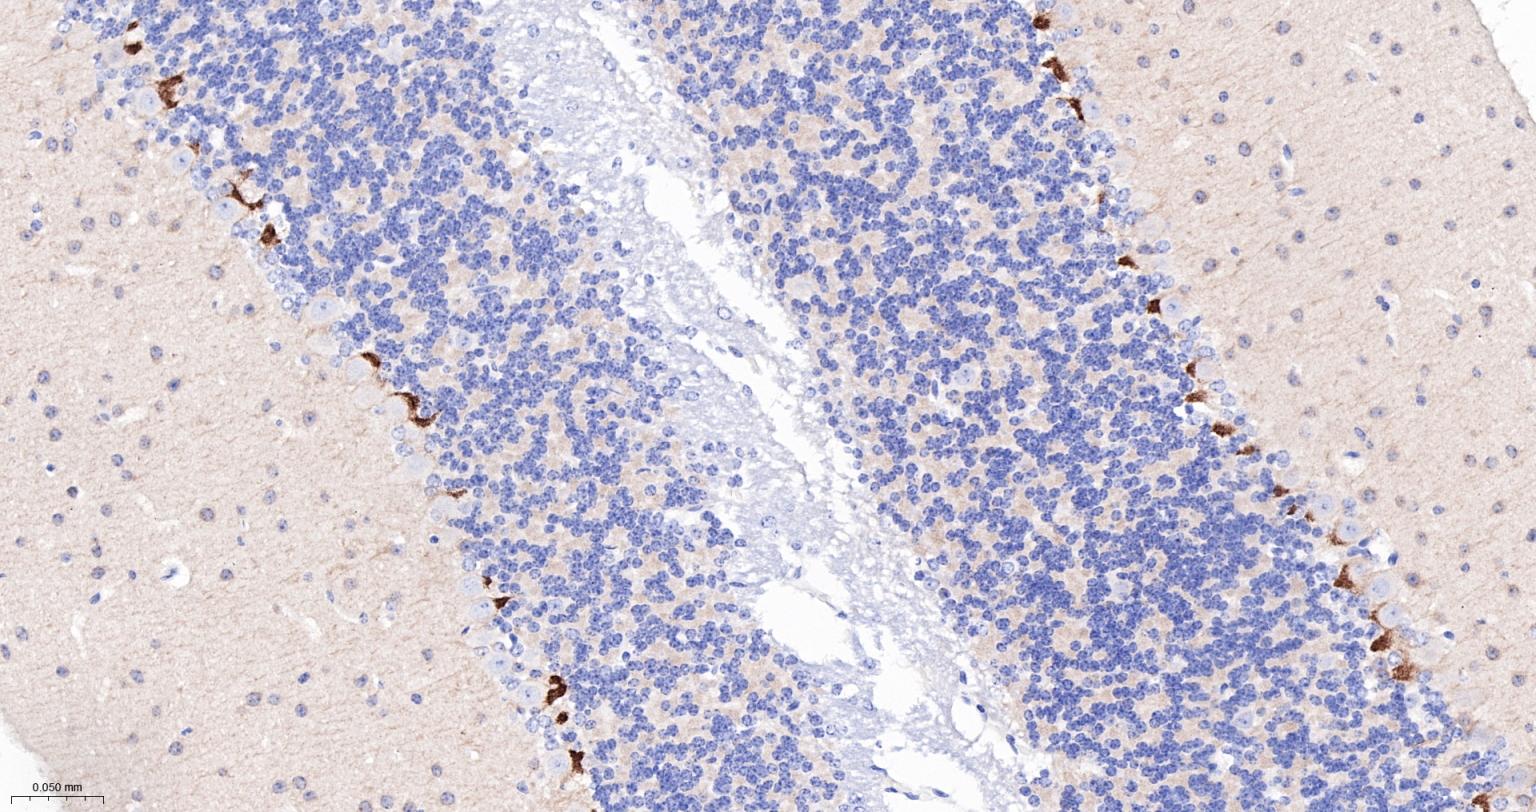

Paraformaldehyde-fixed, paraffin embedded Rat Cerebellum; Antigen retrieval by boiling in sodium citrate buffer (pH6.0) for 15 min; The section was incubated with PSD95 Monoclonal Antibody, Unconjugated (bsm-55665R) at 1:200 overnight at 4°C, followed by conjugation to the bs-0295G-HRP and DAB (C-0010) staining.

Paraformaldehyde-fixed, paraffin embedded Mouse Cerebellum; Antigen retrieval by boiling in sodium citrate buffer (pH6.0) for 15 min; The section was incubated with PSD95 Monoclonal Antibody, Unconjugated (bsm-55665R) at 1:200 overnight at 4°C, followed by conjugation to the bs-0295G-HRP and DAB (C-0010) staining.